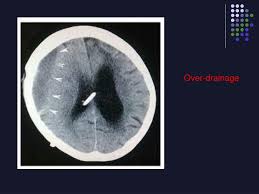

This condition occurs when excess cerebrospinal fluid csf collects in the brain s ventricles. Ventriculoperitoneal shunt learn all about ventriculoperitoneal shunt procedure recovery cost and question answer. Vp shunts is the property of its rightful owner.

Vp ventriculoperitoneal shunting is a surgical procedure for treating a medical condition called hydrocephalus which occurs due to excessive fluid accumulation in the ventricles of the brain. Dc shunts 1 located in delhi india we stand tall as the manufacturer supplier and exporter of dc shunts in the global markets. Ventriculoperitoneal vp shunt procedure.